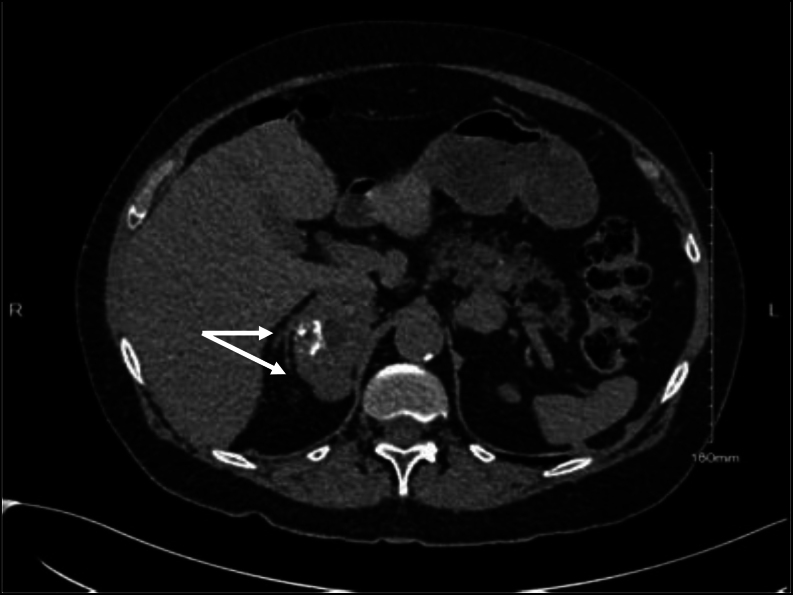

Summary: Adrenocortical carcinoma (ACC) is a rare malignant tumour arising from the adrenal cortex, with an estimated annual incidence of one to two patients per million. Ectopic ACCs are extremely rare. The majority of ACCs are sporadic; however, ACC has been linked with genetic disease processes, including multiple endocrine neoplasia type-1 (MEN-1). We present the case of a 66-year-old lady referred with newly diagnosed diabetes on a background of primary hyperparathyroidism. Examination revealed Cushingoid features, and hormonal evaluation confirmed ACTH-independent Cushing's syndrome. Morning cortisol after a 1 mg overnight dexamethasone suppression test was 548 nmol/L with an undetectable ACTH <3.0 pg/mL. Dehydroepiandrosterone sulphate was 5.3 μmol/L and androstenedione 3.49 nmol/L, both of which were normal. Testosterone was suppressed at <0.4 nmol/L. Imaging revealed a 6 × 6 × 4.5 cm right-sided presumed adrenal lesion, a pancreatic lesion (2.5 × 1.6 cm), and bilateral pulmonary nodules (0.9 × 0.8 cm, 0.7 × 0.6 cm, 0.3 cm). Right adrenalectomy was performed, and histology was consistent with an extra-adrenal ACC (Weiss score 5/9) within the peri-adrenal adipose tissue. The resected adrenal gland was normal. Lung biopsy confirmed metastatic ACC tissue, and endoscopic ultrasound-guided biopsy of the pancreatic lesion revealed a pancreatic neuroendocrine tumour, which was confirmed biochemically to be an insulinoma. Genetic assessment confirmed MEN-1. This case highlights the importance of screening for MEN-1 in at-risk patients and the need for close clinical follow-up. To our knowledge, this is the first case report of extra-adrenal ACC in MEN-1 syndrome.

Learning points: Adrenal lesions in MEN-1 syndrome have significant malignant potential. Newly diagnosed lesions should be followed closely with short-interval imaging, and a lower threshold for surgical removal is suggested. Primary hyperparathyroidism is often the earliest laboratory or clinical manifestation of MEN-1 syndrome. A detailed medical and family history is vital in order to appropriately identify patients at risk of MEN-1. To our knowledge, this is the first case report of extra-adrenal adrenocortical carcinoma in MEN-1 syndrome.